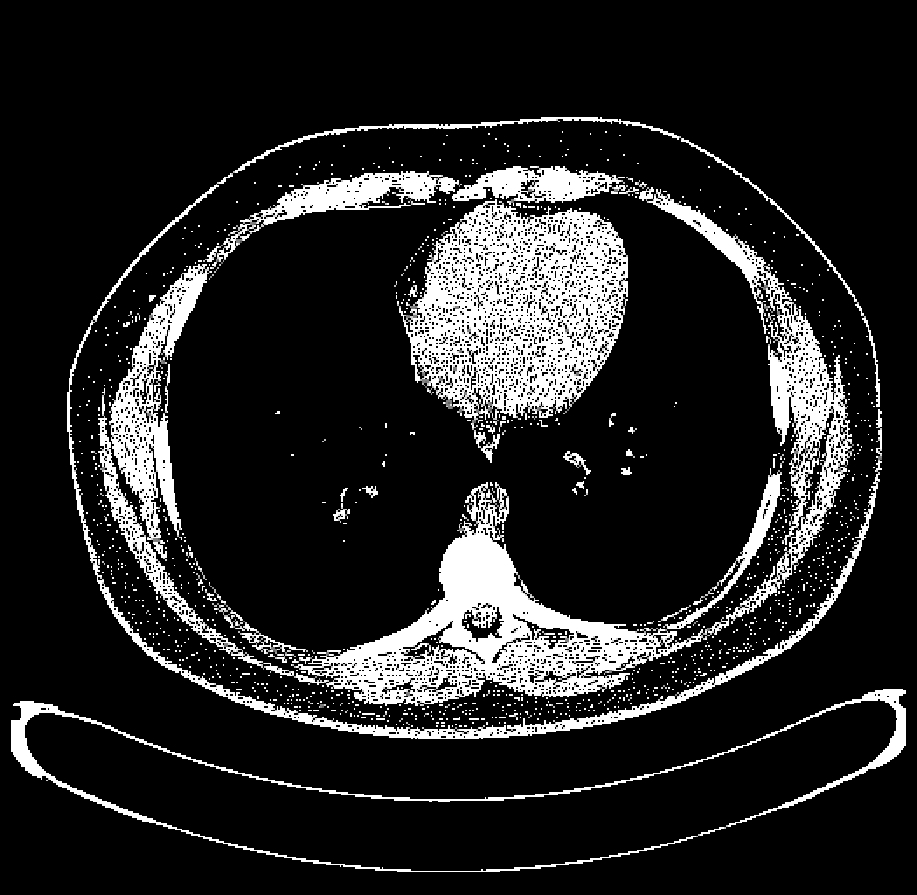

正常人脑部CT横断面图像,可以清晰地分辨灰质、白质和脑脊液

CT的革命性突破在于断层成像(Tomography)——它不是拍摄整个身体的投影,而是一层一层地扫描,每一层都是一个横断面(就像切面包一样)。

CT的基本工作流程:

- 多角度投影:X射线管和探测器围绕患者旋转,从数百个不同角度拍摄X射线"照片"(投影)

- 测量衰减:每个角度都测量X射线穿过身体后的强度变化

- 计算机重建:利用数学算法(如滤波反投影),从这些投影数据中重建出横断面图像

- 三维成像:将多个横断面堆叠起来,就得到了三维的体数据